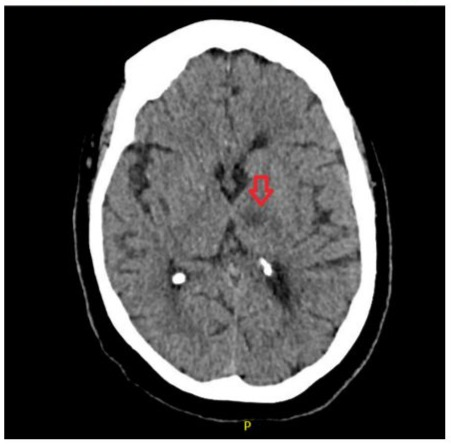

An urgent CT head (Figure 1) was arranged which confirmed acute/ subacute infarct in left thalamus following which an urgent referral to the stroke team was made. Upon assessment by the stroke team, patient had a BP of 132/91, National Institute of Health Stroke Scale (NIHSS) score of 6/42 and modified Rankin Scale (mRS) of 1/6. Clinical examination revealed confusion and word finding difficulty which led to the NIHSS score of 6. A decision was made to admit the patient to hyper-acute stroke unit (HASU) locally

Figure 1: CT head demonstrating focal hypodensity in the left thalamus (red arrow) with appearances concerning for acute/ subacute infarct possibly on a background of small chronic infarct.